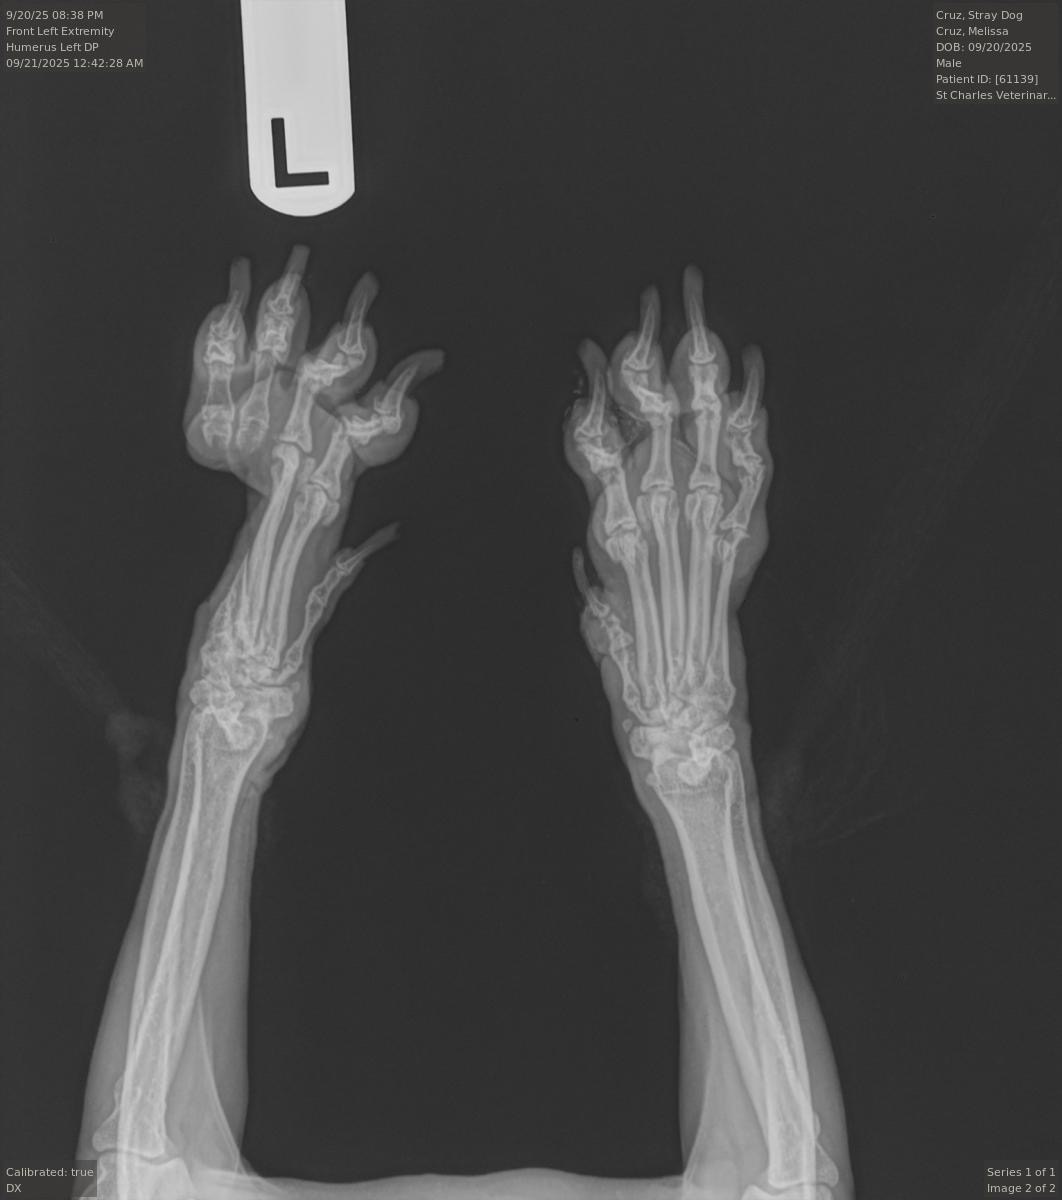

Shadow has been through so much, but what breaks my heart most is what the vet discovered: two of his toes have no bones left. They’re just fragile, empty shells that could tear or get infected at any moment. It appears to be blunt force trauma that caused this injury. To save him from future pain, those toes will need to be amputated.